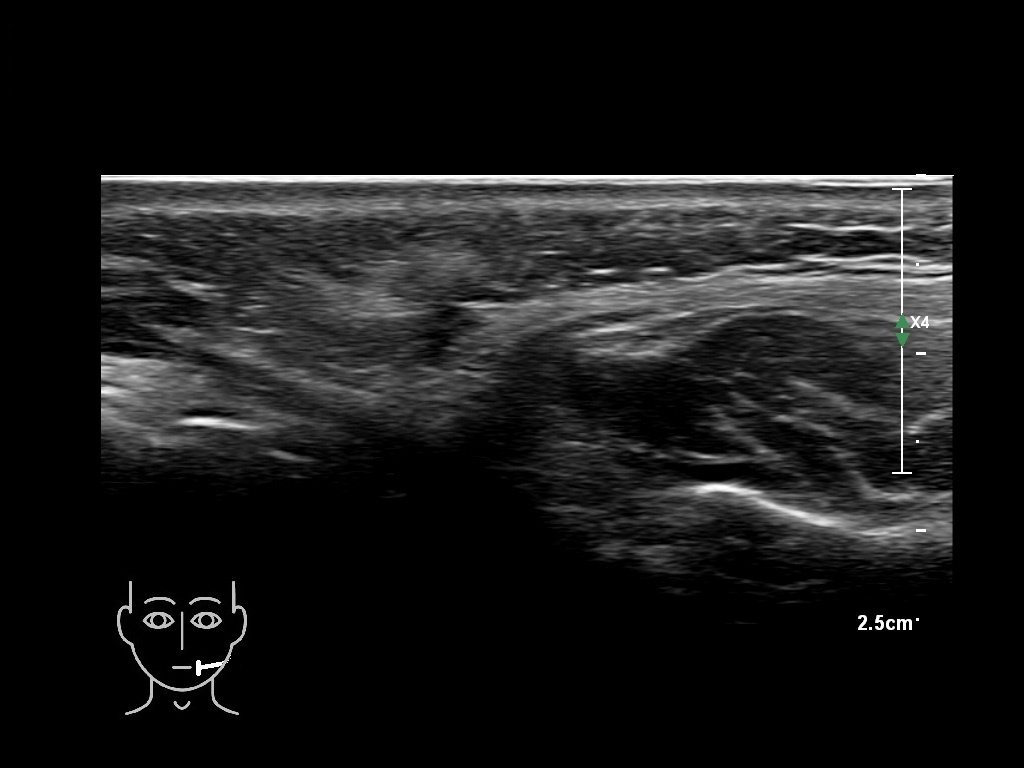

Draw in the image on the right where the fillers are located. To check if your answer is correct, please click on the secondary image.